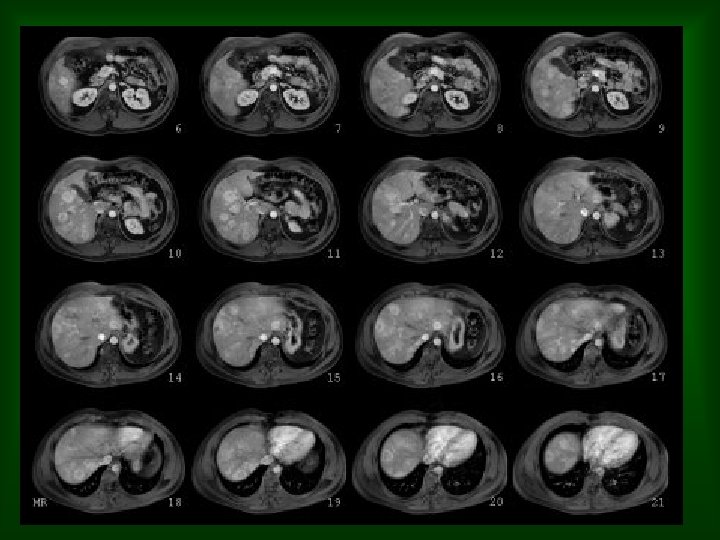

Imagen Tc axial de hígado en fase portal en paciente con adenoca colorectal. Lesión sólida , hipovascular mal definida, inespecífica aunque por su tamaño y anteceentes del paciente sugestiva de metástasis. Estudio axial RM T 1 FS antes y después de administración de contraste. La lesión se define mucho mejor con la RM incluso en el estudio basal. Tras la administración de contraste la lesión capta de forma tenue en su perifería lo que es más característico de metastasis.

METASTASIS HEPÁTICAS • RM – – – Sensibilidad similar o ligeramente superior a la de TC Hiperintensas T 2 / hipointesnas T 1 Estudio dinámico tras administracion Gd. Secuencias T 1 gradiente (3 D) con supresión grasa. Contrastes específicos: incrementa la sensibilidad ( no específico) • No realce con ferrumoxidos. ( No SER) • No realce con manganeso. ( No hepatocitos)